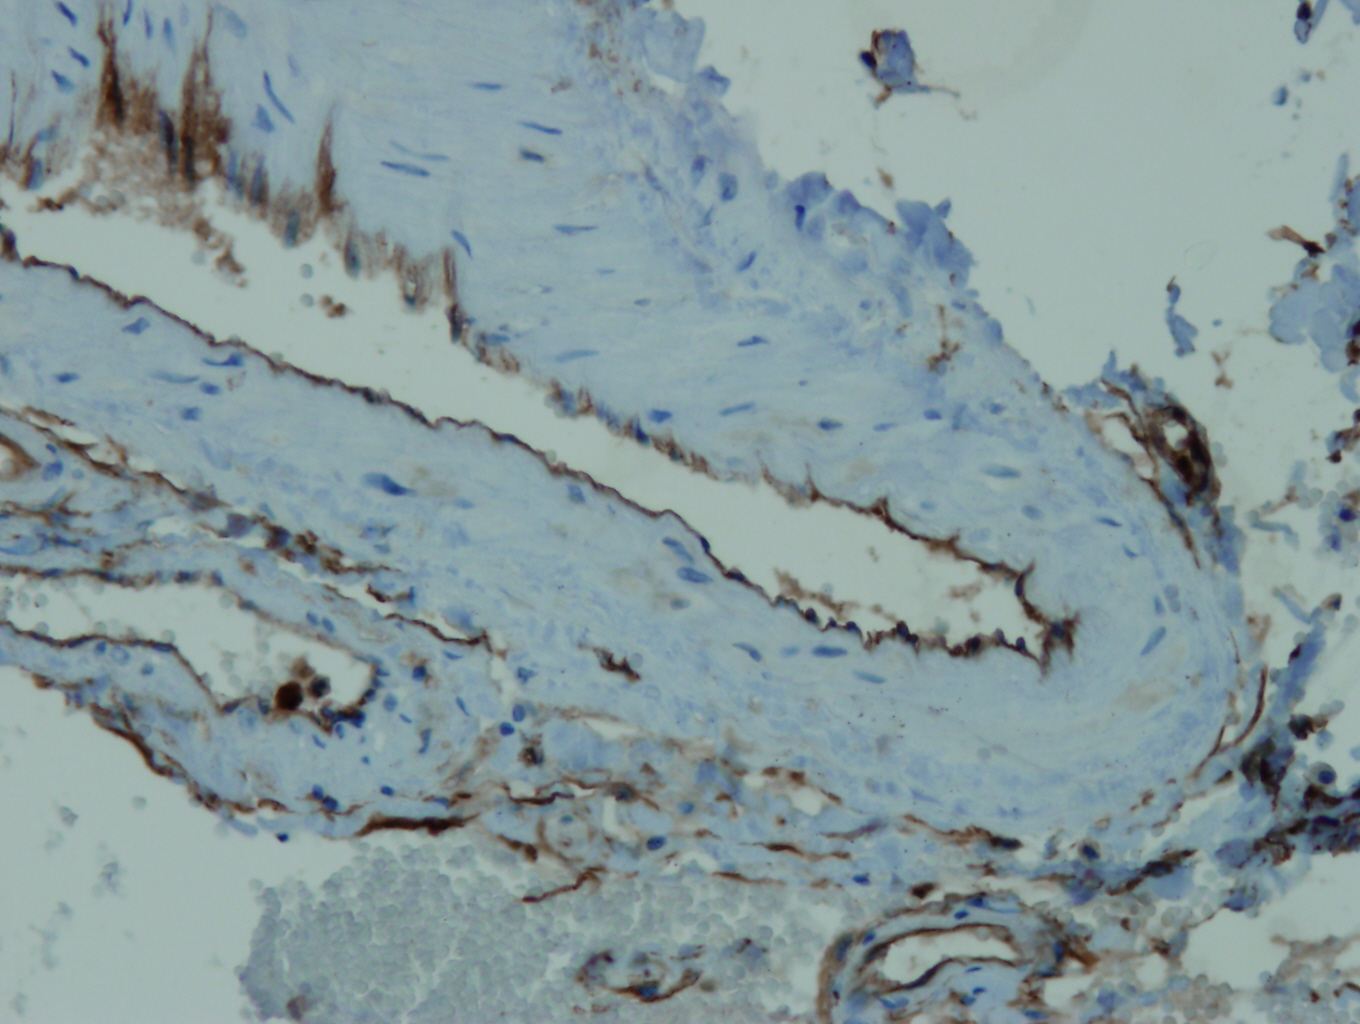

Anti-CD34

Králičia klonálna protilátka

Kód produktu:DB 151 Kategória:IHC-P

Aplikácia

IHC-P, riedenie 1:100

Galéria

db151a db151b